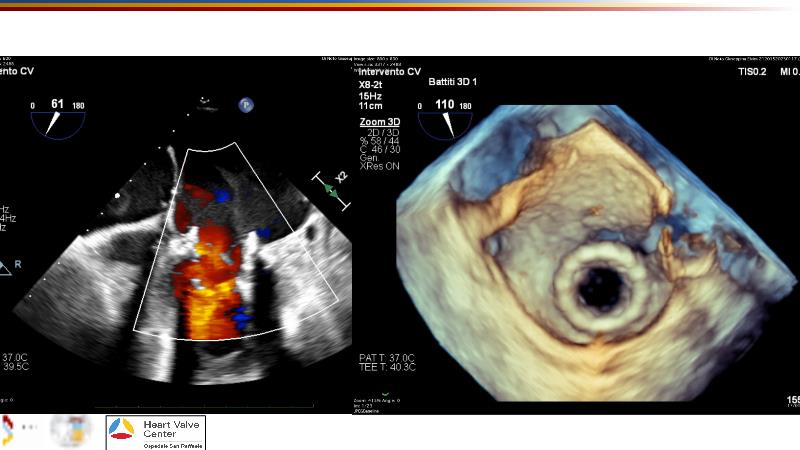

Explore cutting-edge transcatheter valve interventions for mitral and aortic valve disorders, including valve-in-valve procedures and management strategies for paravalvular leakages, and learn about diagnosing and treating mitral annular calcification and transcatheter options in infective endocarditis.

- To manage patients with mixed and multiple valvular heart disease: from risk stratification to therapeutic decision-making

- To get tips and tricks for guidance of transcatheter intervention